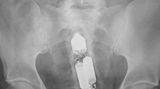

Diese Dinge gehören dort eigentlich nicht hin: Immer wieder passieren Unfälle, wenn Menschen sich zur sexuellen Stimulation über den After Gegenstände in den Darm einführen. Ob Orangen, Spraydosen oder Kaffeebüchsen - der Fantasie sind dabei offenbar keine Grenzen gesetzt.

Die Webseite radiopaedia.org zeigt, welche Dinge Ärzte auf Röntgenbildern schon entdeckt haben. Die Aufnahmen wirken skurril und erschreckend zugleich und machen deutlich, wie weit die eingeführten Dinge bereits in den mescnhlichen Darm vordringen können.

Aber Glück im Unglück für die Patienten: Die Gegenstände können meist ohne Operation entfernt werden. Sehen Sie hier einige der spektakulärsten Röntgenaufnahmen. Da runzeln selbst Chirurgen die Stirn.